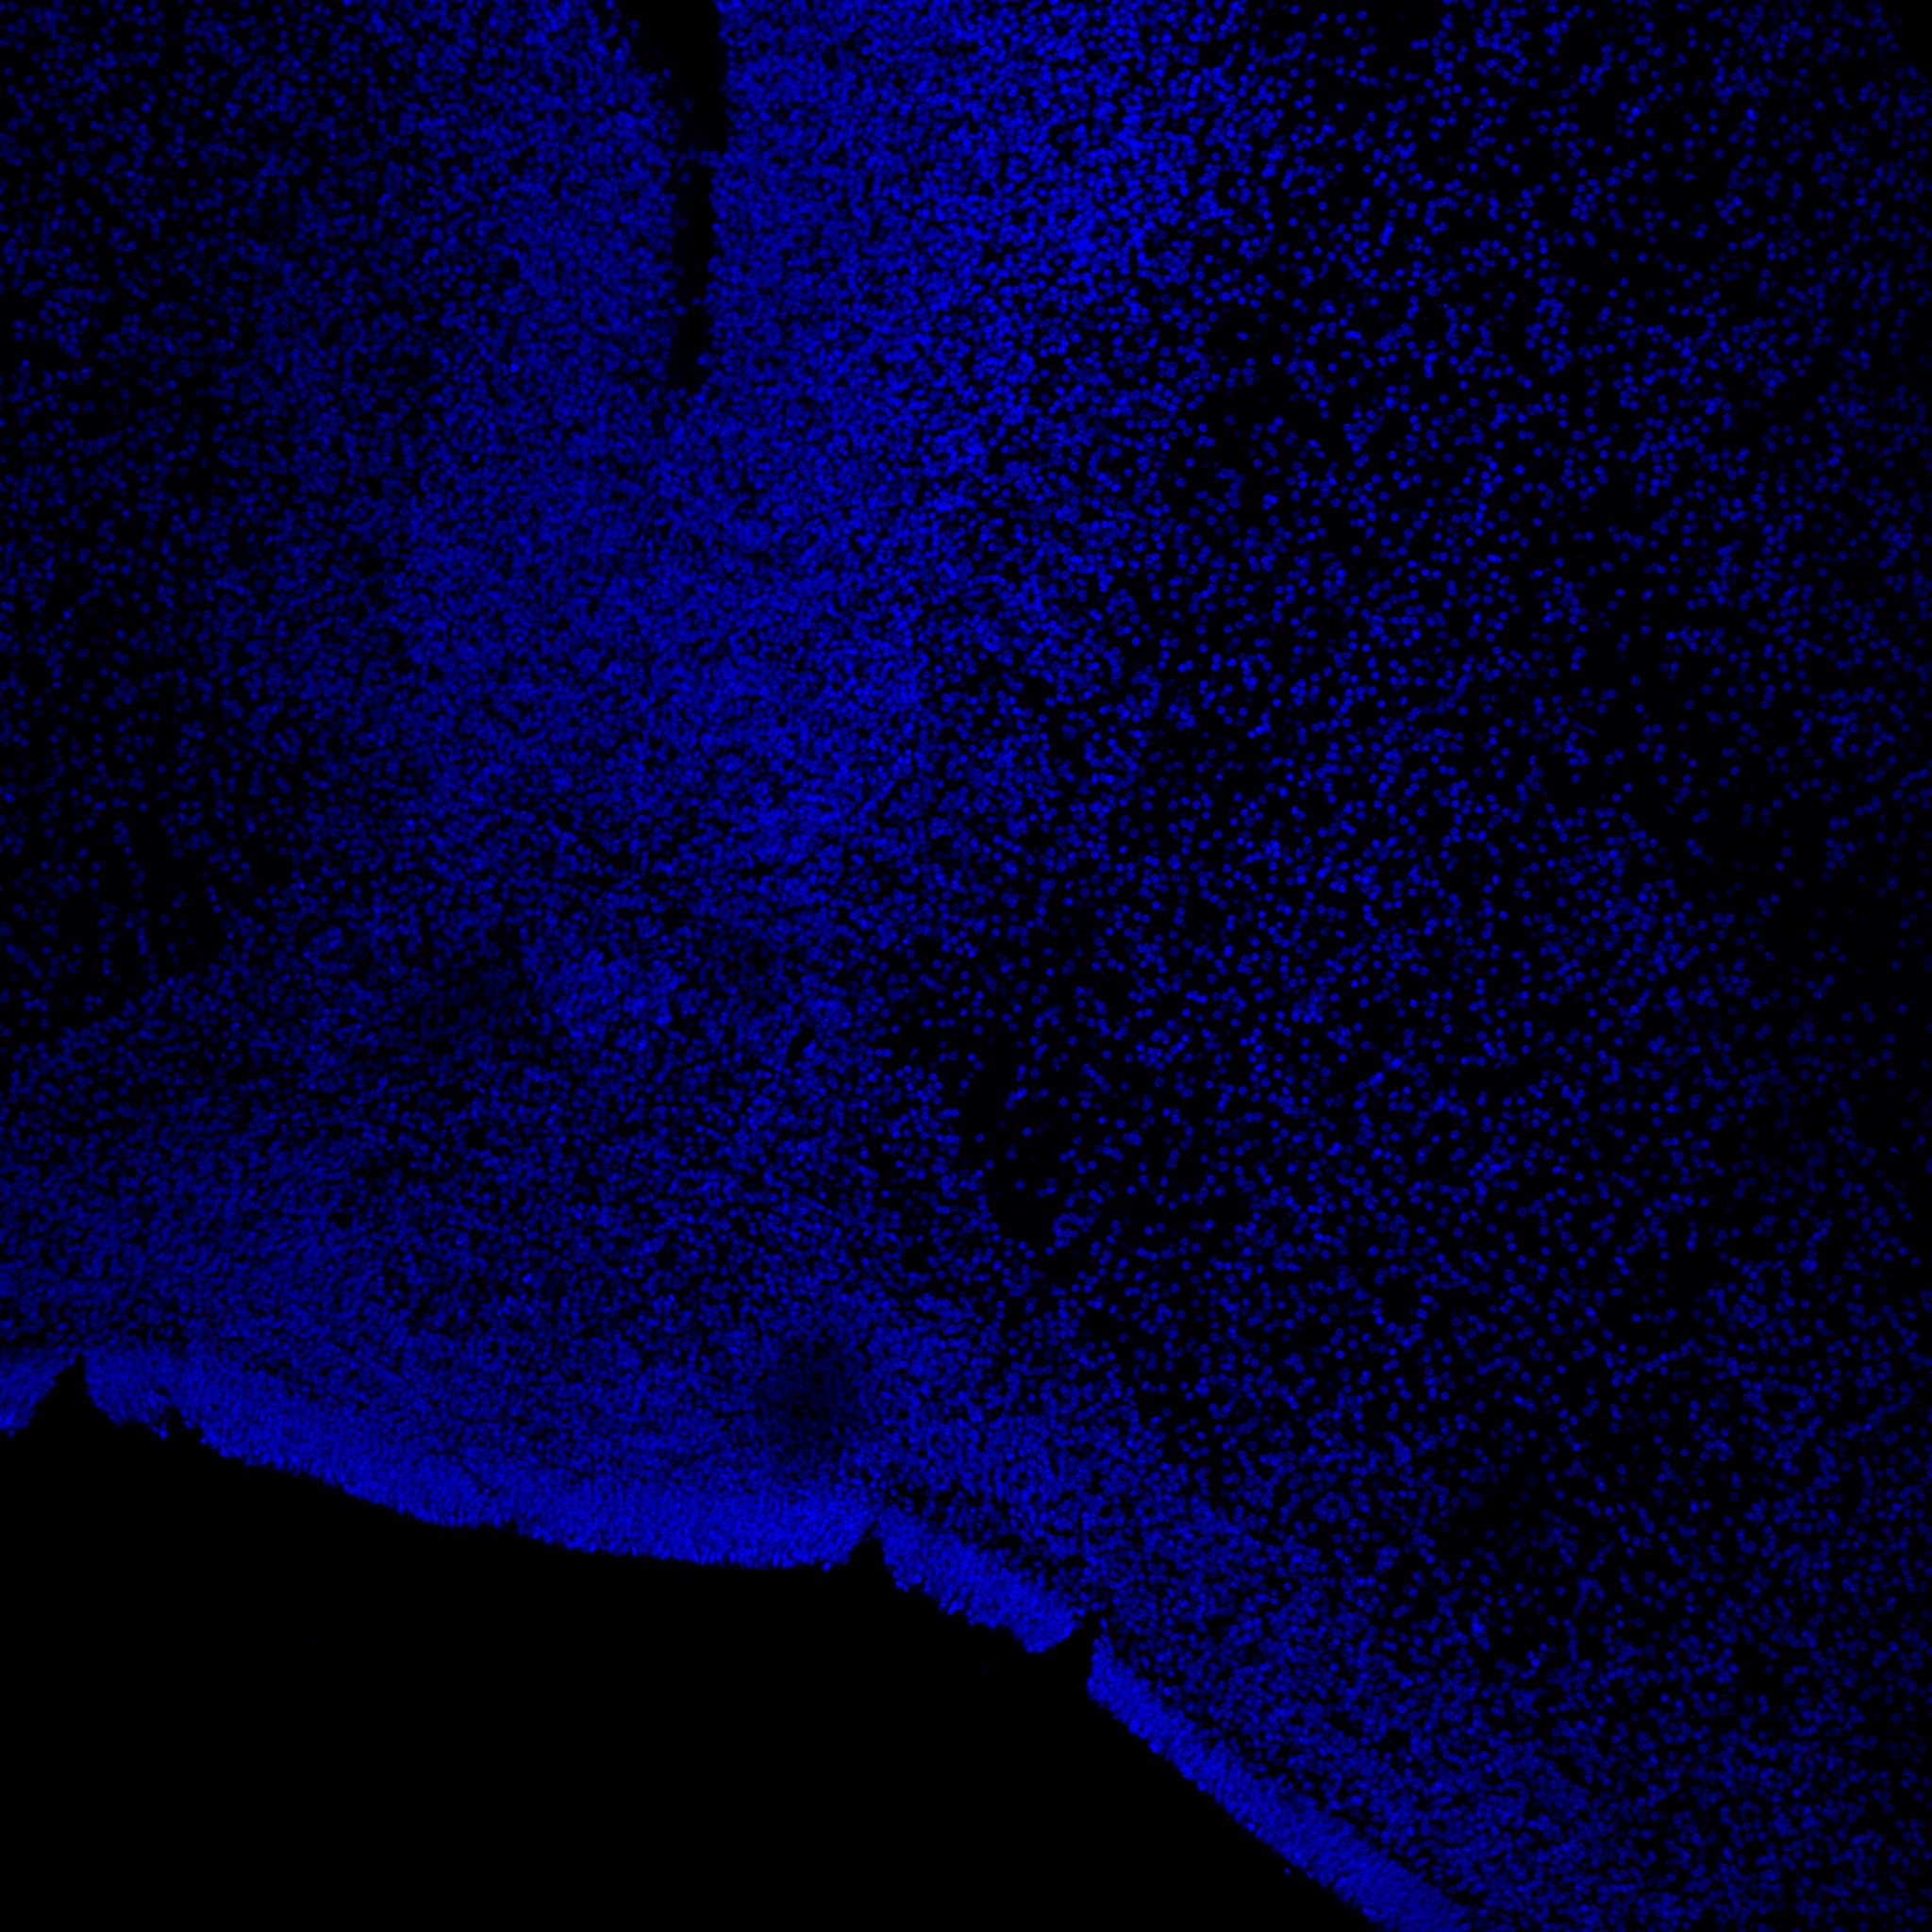

DAPI

11PCW human midbrain

MAP2

TH

Merged